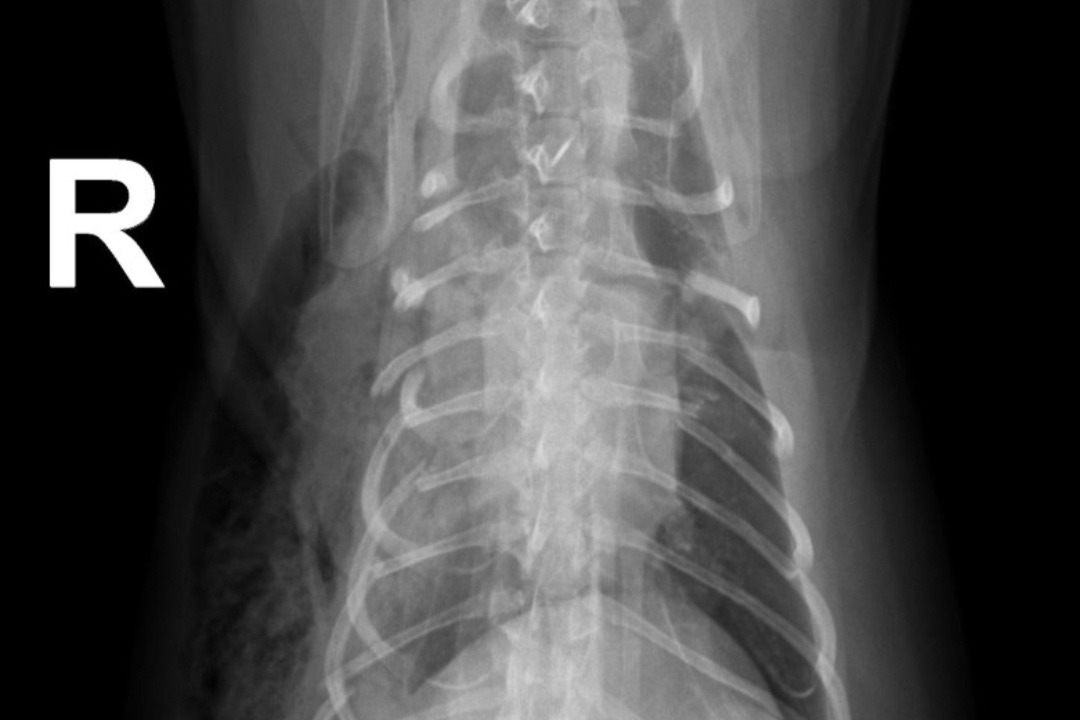

*Romeo's X-Rays*Our 4 year old cat Romeo has been SEVERELY injured and the vet stated that she believes he was crushed. When we came home after bringing him to the hospital, we realized that our boxspring was broken, so we believe that it fell onto him and crushed him. He has broken ribs, a shattered femur, etc. He will need to have his leg amputated, which in itself is $7000 and would be $17,000 if we decided to keep the leg and have them try to fix it and we genuinely cannot afford it.. And those prices are for his leg alone, it doesn't include the cost for his ribs or medications, or the $2000 a night to stay at the hospital. Please help us save our boy.. We cannot live in a world without him.. He's the most special cat in the entire world and our hearts are breaking. If we cannot afford the surgeries, then we will have to put him down. Please help in any way you can..